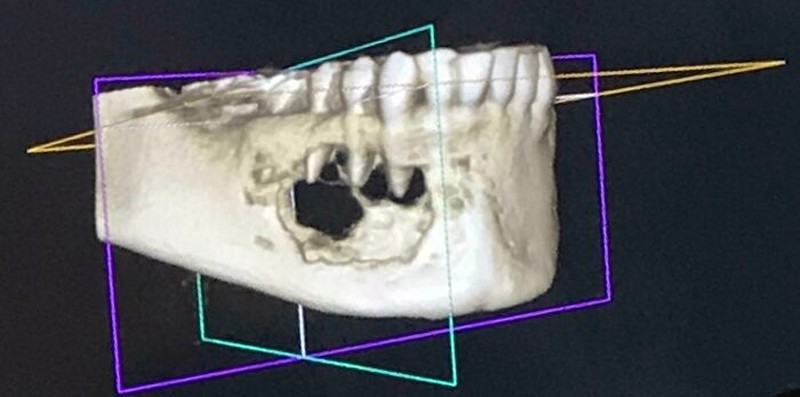

Foto scan CT memperlihatkan kondisi rahang yang dimakan tumor. Foto: Boredpanda